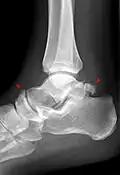

Ankle

Accessory bones of the ankle.[13]

Accessory bones at the ankle mainly include:

• Os subtibiale, with a prevalence of approximately 1%.[14] It is a secondary ossification center of the distal tibia that appears during the first year of life, and which in most people fuses with the shaft at approximately 15 years in females and approximately 17 years in males.[14]

• Os subfibulare, with a prevalence of approximately 0.2%.[15]

Os trigonum (further described below) may also be seen on an ankle X-ray.